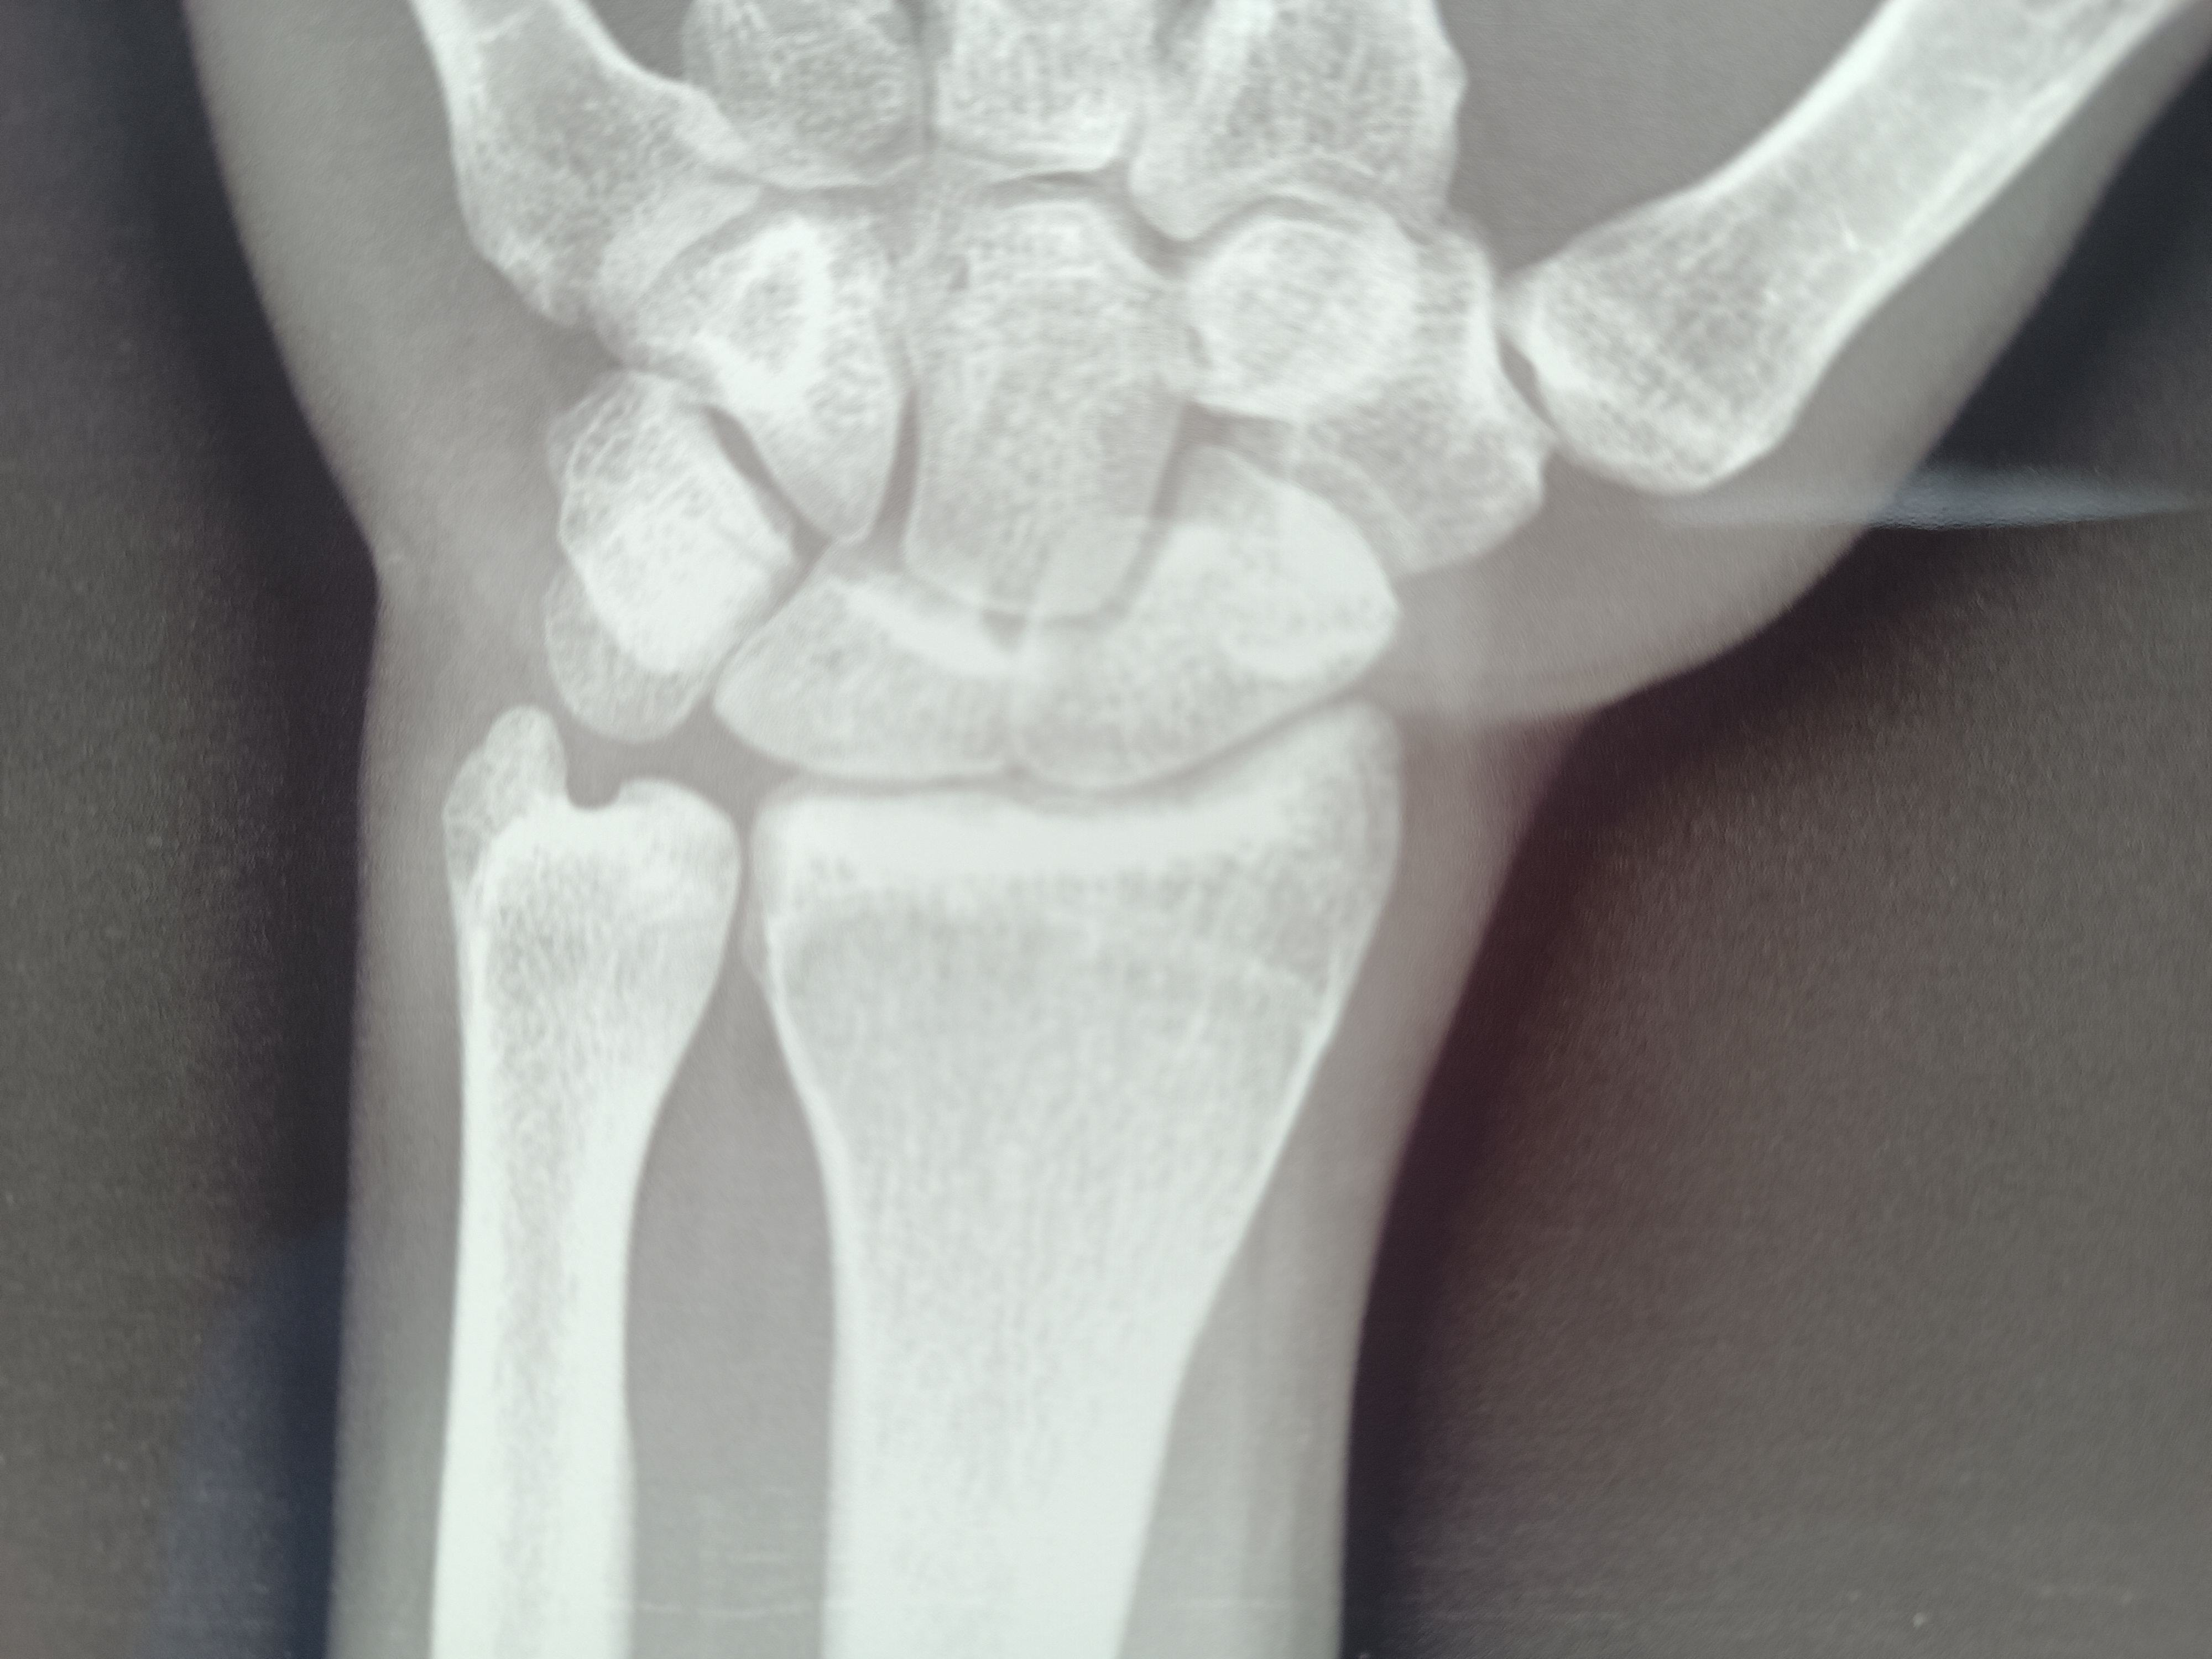

صفائح النمو هل اكتملت

اريد معرف اذ اغلقت صفائح النمو بشكل كامل أم لا يزال لدي فرصة لزيادة الطول.